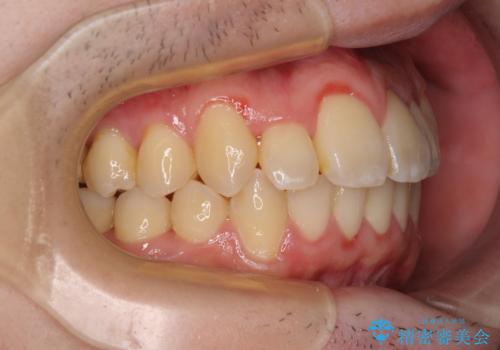

前歯のクロスバイトや八重歯の他に、左右最後臼歯のシザーズバイト(鋏状咬合)が認められました。

シザーズバイトは強く咬合する奥歯を移動させるため、多くの場合においてワイヤー矯正の装置のみでは改善が困難となります。

奥歯の咬み合わせ改善は治療初期からしっかりとアプローチする必要があるため、補助装置を積極的に利用します。